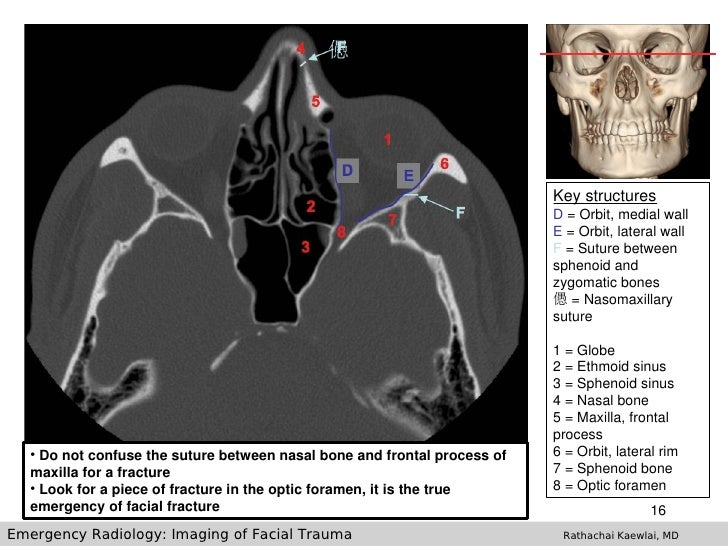

Complex facial fractures

Complex facial fractures 142 photos